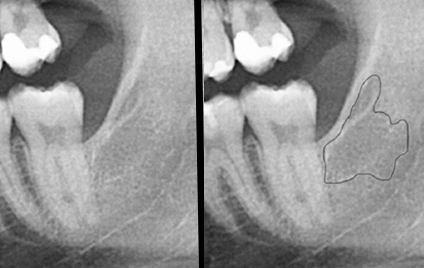

Die Diagnose einer Osteolyse im Kiefer ist schwierig. Mit einer herkömmlichen Röntgenübersichtsaufnahme können diese Knochenerweichungen nur in den seltensten Fällen erkannt, sondern eher nur vermutet werden. Eine sichere Diagnostik dieser Knochenerweichung erlaubt ausschließlich eine digitale Volumentomografie (DVT) oder eine Untersuchung mittels Magnetresonanz (MRT).